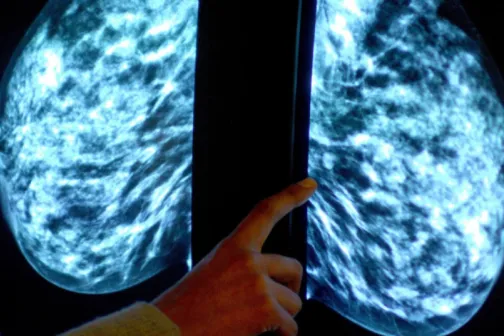

Imagine 16/11/2022 -11:33 Sănătate Europa se va confrunta cu o ”epidemie de cancer”, avertizează oncologii. Un milion de cazuri ar fi rămas nediagnosticate în pandemie